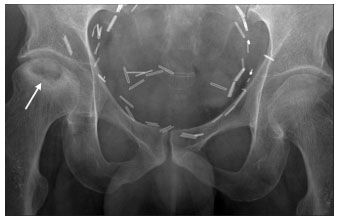

Figure 1.Anterior-posterior plain radiograph of the pelvis with subcortical lucency surrounded by sclerosis (arrow) indicating stage III osteonecrosis according to the classification system by Arlet, Ficat, and Hungerford (as reported in Steinberg and colleagues10: stage I, no changes; stage II, cystic and/or sclerotic changes without subcortical lucency; stage III, subcortical lucency and subchondral fracture; stage IV, subchondral collapse; stage V, joint narrowing. Surgical clips reflect previous radical cystectomy in this patient.

He has had mild, intermittent right hip discomfort for the past 6 months. Findings from previous physical examinations were unrevealing, and he retained full mechanical function, initially prompting conservative treatment with anti-inflammatory medication. A heel lift was placed in his right shoe, which offered mild relief. However, his symptoms progressed to a deep, throbbing pain radiating to his right groin, which worsened with weight-bearing activity. Plain radiographs followed by MRI of his pelvis confirmed the diagnosis of osteonecrosis (Figures 1, 2, and 3). He underwent total hip arthroplasty, with complete resolution of his symptoms.